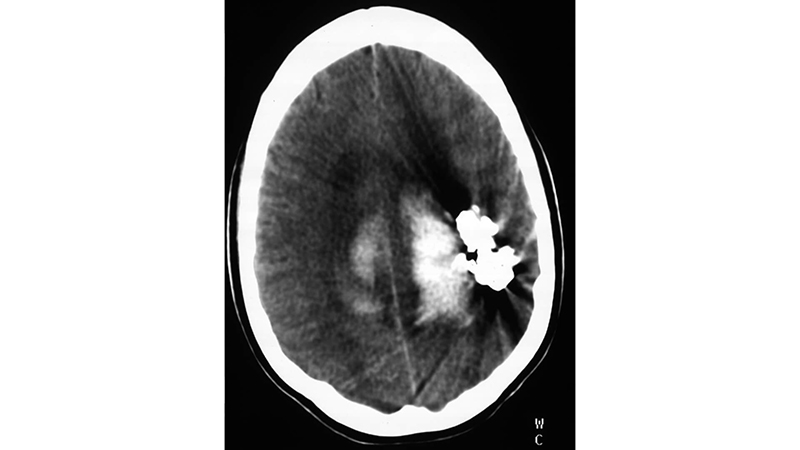

- Αξονική τομογραφία αμέσως μετά τον εμβολισμό. Διακρίνεται το εκμαγείο του εμβολικού υλικού.